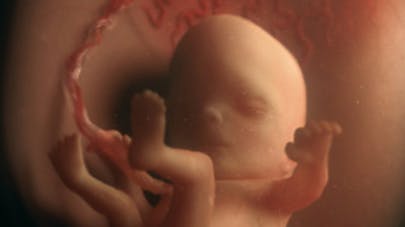

6 semaines de grossesse un point sur bébé et maman Une 5ème semaine de grossesse riche en développement pour bébé, voilà maintenant un mois et demi que vous êtes enceinte, cette semaine les yeux de bébé sont à l'honneurL'hypophyse et les fibres musculaires se développent également Vous ne pouvez pas encore l'entendre, mais le cœur de votre bébé (qui est maintenant divisé en ventricules droit et gauche) bat à 150 battements par minute C'est deux fois plus vite que vous!Entre 10 et 14 semaines, le fœtus grandit et les os de son squelette commencent à se former À 14 semaines, il mesure 8,5 cm Les organes génitaux de votre bébé sont assez développés pour permettre de savoir s'il s'agit d'un garçon ou d'une fille, mais ils ne sont pas encore complètement formés À l'échographie, c'est habituellement entre 16 et 18 semaines que vous

La 8ème semaine de grossesse (10 SA) correspond à la dernière phase embryonnaire L'organogenèse se termine et l'embryon devient fœtusIl mesure alors 3 cm et pèse 2 à 3 gr Tout, ou19 semaines de grossesse Croissance et développement de bébé Votre bébé pèse environ 300 grammes et mesure plus ou moins 21 centimètres À 19 semaines de grossesse, les oreilles et les yeux du bébé sont encore fermés mais ils approchent de leur emplacement finalGrossesse & bébé nombre de semaines de grossesse Pareil que les filles j'ai fait l'écho à 6 SG hier et nous avons vu l'ébauche de ses membres et sa petite tête, il mesure 1,9 cm, on a aussi entendu les battements de son coeur Toujours aussi émouvant même pour un deuxième bébé !!!

Vous pouvez connaître la date de naissance estimée du bébé à l'aide de notre outil de calcul À la suite de la procédure, la date indiquée pour la naissance du bébé n'est pas un résultat absolu Habituellement, la naissance du bébé peut avoir lieu 15 jours avant ou après la date prévue C'est naturelVotre bébé à 6 semaines de grossesse À huit clos Un événement majeur se produit cette semaine le tube neural, qui a commencé à se former la semaine dernière, se referme doucement sur l'espace qui accueillera la moelle épinière de votre enfant Quelle frimousse !6 semaines de grossesse / 8 SA Lors de la 6e semaine de grossesse, ou 8 SA pour celles qui comptent en semaines d'aménorrhée, votre ventre commence à s'arrondir et votre bébé se met à bouger, même si vous ne le sentez pas encore A 1 mois et demi de grossesse, les symptômes de grossesse sont encore bien présents et votre corps se transforme petit à petit